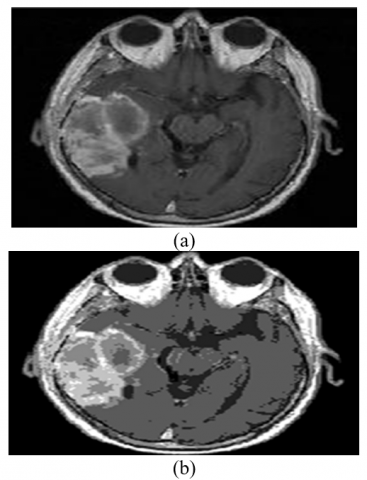

The second step of the pre-processing required the removal of extra skull that was present in the input image. This skull was not use for further processing. This was done with the help of mathematical morphological operations. The morphological process involved erosion, dilation, opening and closing of the images. The output obtained from the mathematical morphological operations is shown in Figure 2.

Figure 2. (a) Input image to morphology process with bones, (b) Output after the morphology process containing no bone